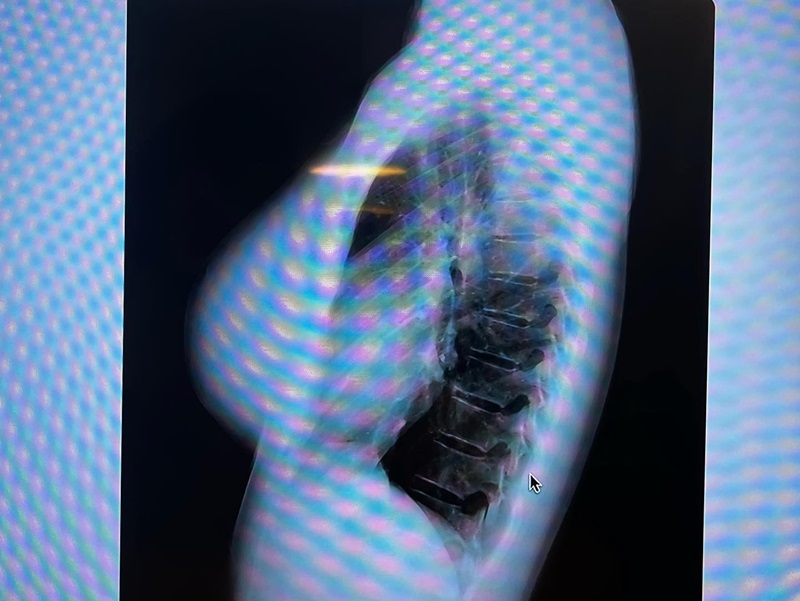

ดาราสาวญี่ปุ่นชื่อดัง เจ้าของหน้าอกคัพ L โดนถามไม่ไหว ของแท้แม่ให้มาไหม คับอกคับใจ โชว์ให้ดูถึงกระดูก ตบ ๆ กันไป

ด้วยความที่หน้าอกของเธอนั้นใหญ่แบบอลังการ ทำให้ดาราสาวสุดแซ่บรายนี้ มักจะเจอแต่คำถามเดิม ๆ อยู่บ่อยครั้ง นั่นคือ "หน้าอกนี้เป็นธรรมชาติ เป็นของแท้หรือเปล่า" จนล่าสุด เมื่อไม่นานมานี้ ฟูมินะ ได้ออกมาโพสต์ภาพยืนยันกันแบบจัดเต็ม ให้เห็นกันถึงไส้ถึงพุงกันเลยทีเดียว

โดยจากภาพเอกซเรย์ดังกล่าว แสดงให้เห็นว่า ไม่มีวัสดุเต้านมเทียม หรือสารแปลกปลอมที่หน้าอกของเธอ จึงพิสูจน์ได้ชัดว่าคัพ L ของเธอ เป็นของแท้แม่ให้มาแน่นอน